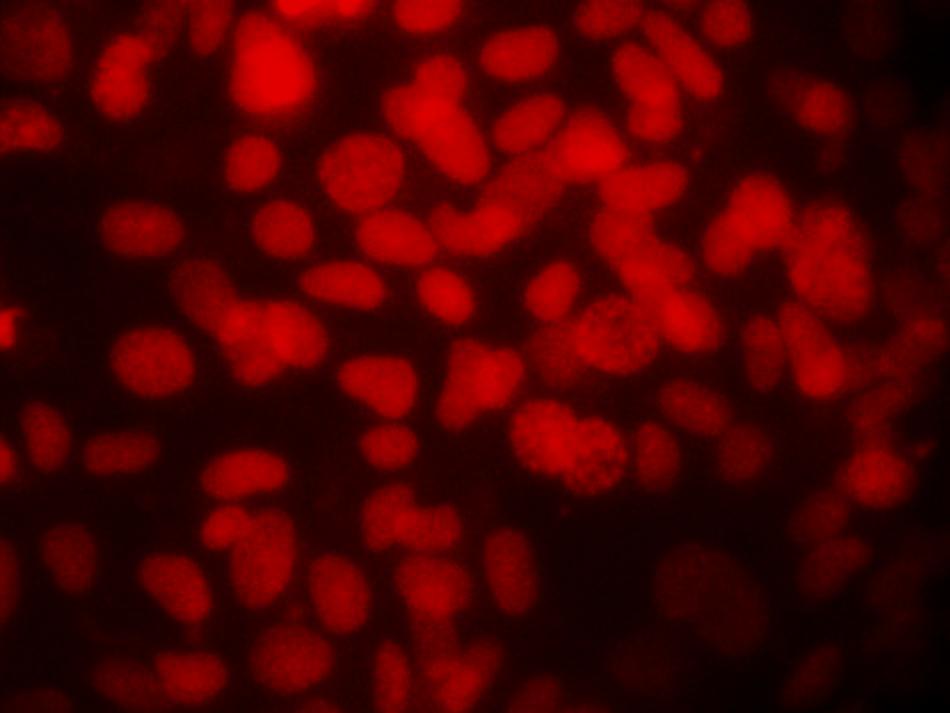

The fluorescence micrograph of the control and Silver nanoparticles treated Hep3B cells assessed for nuclear morphology after staining with propidium iodide stain. The control untreated Hep3B cells (Figure 5a) shows clear nuclei. The highly condensed and fragmented nuclei that are the index of apoptosis were observed in silver nanoparticles treated cell at different time point 24 h and 48 h (Figure 5b and c). The apoptotic nuclei after treatment with silver nanoparticles found to be increased in a time dependent manner which was clearly revealed by nuclear condensation and fragmentation.

Fig. 5a: Detection of Apoptosis Using PI staining- Hep 3B cell line control

Fig. 5b: 24 hrs after treatment of Hep 3B cell line with IC50 concentration, arrows indicates the cells with fragmented nuclei

Fig. 5c: 48 hrs after treatment of Hep 3B cell line with IC50 concentration, arrows indicates the cells with fragmented nuclei